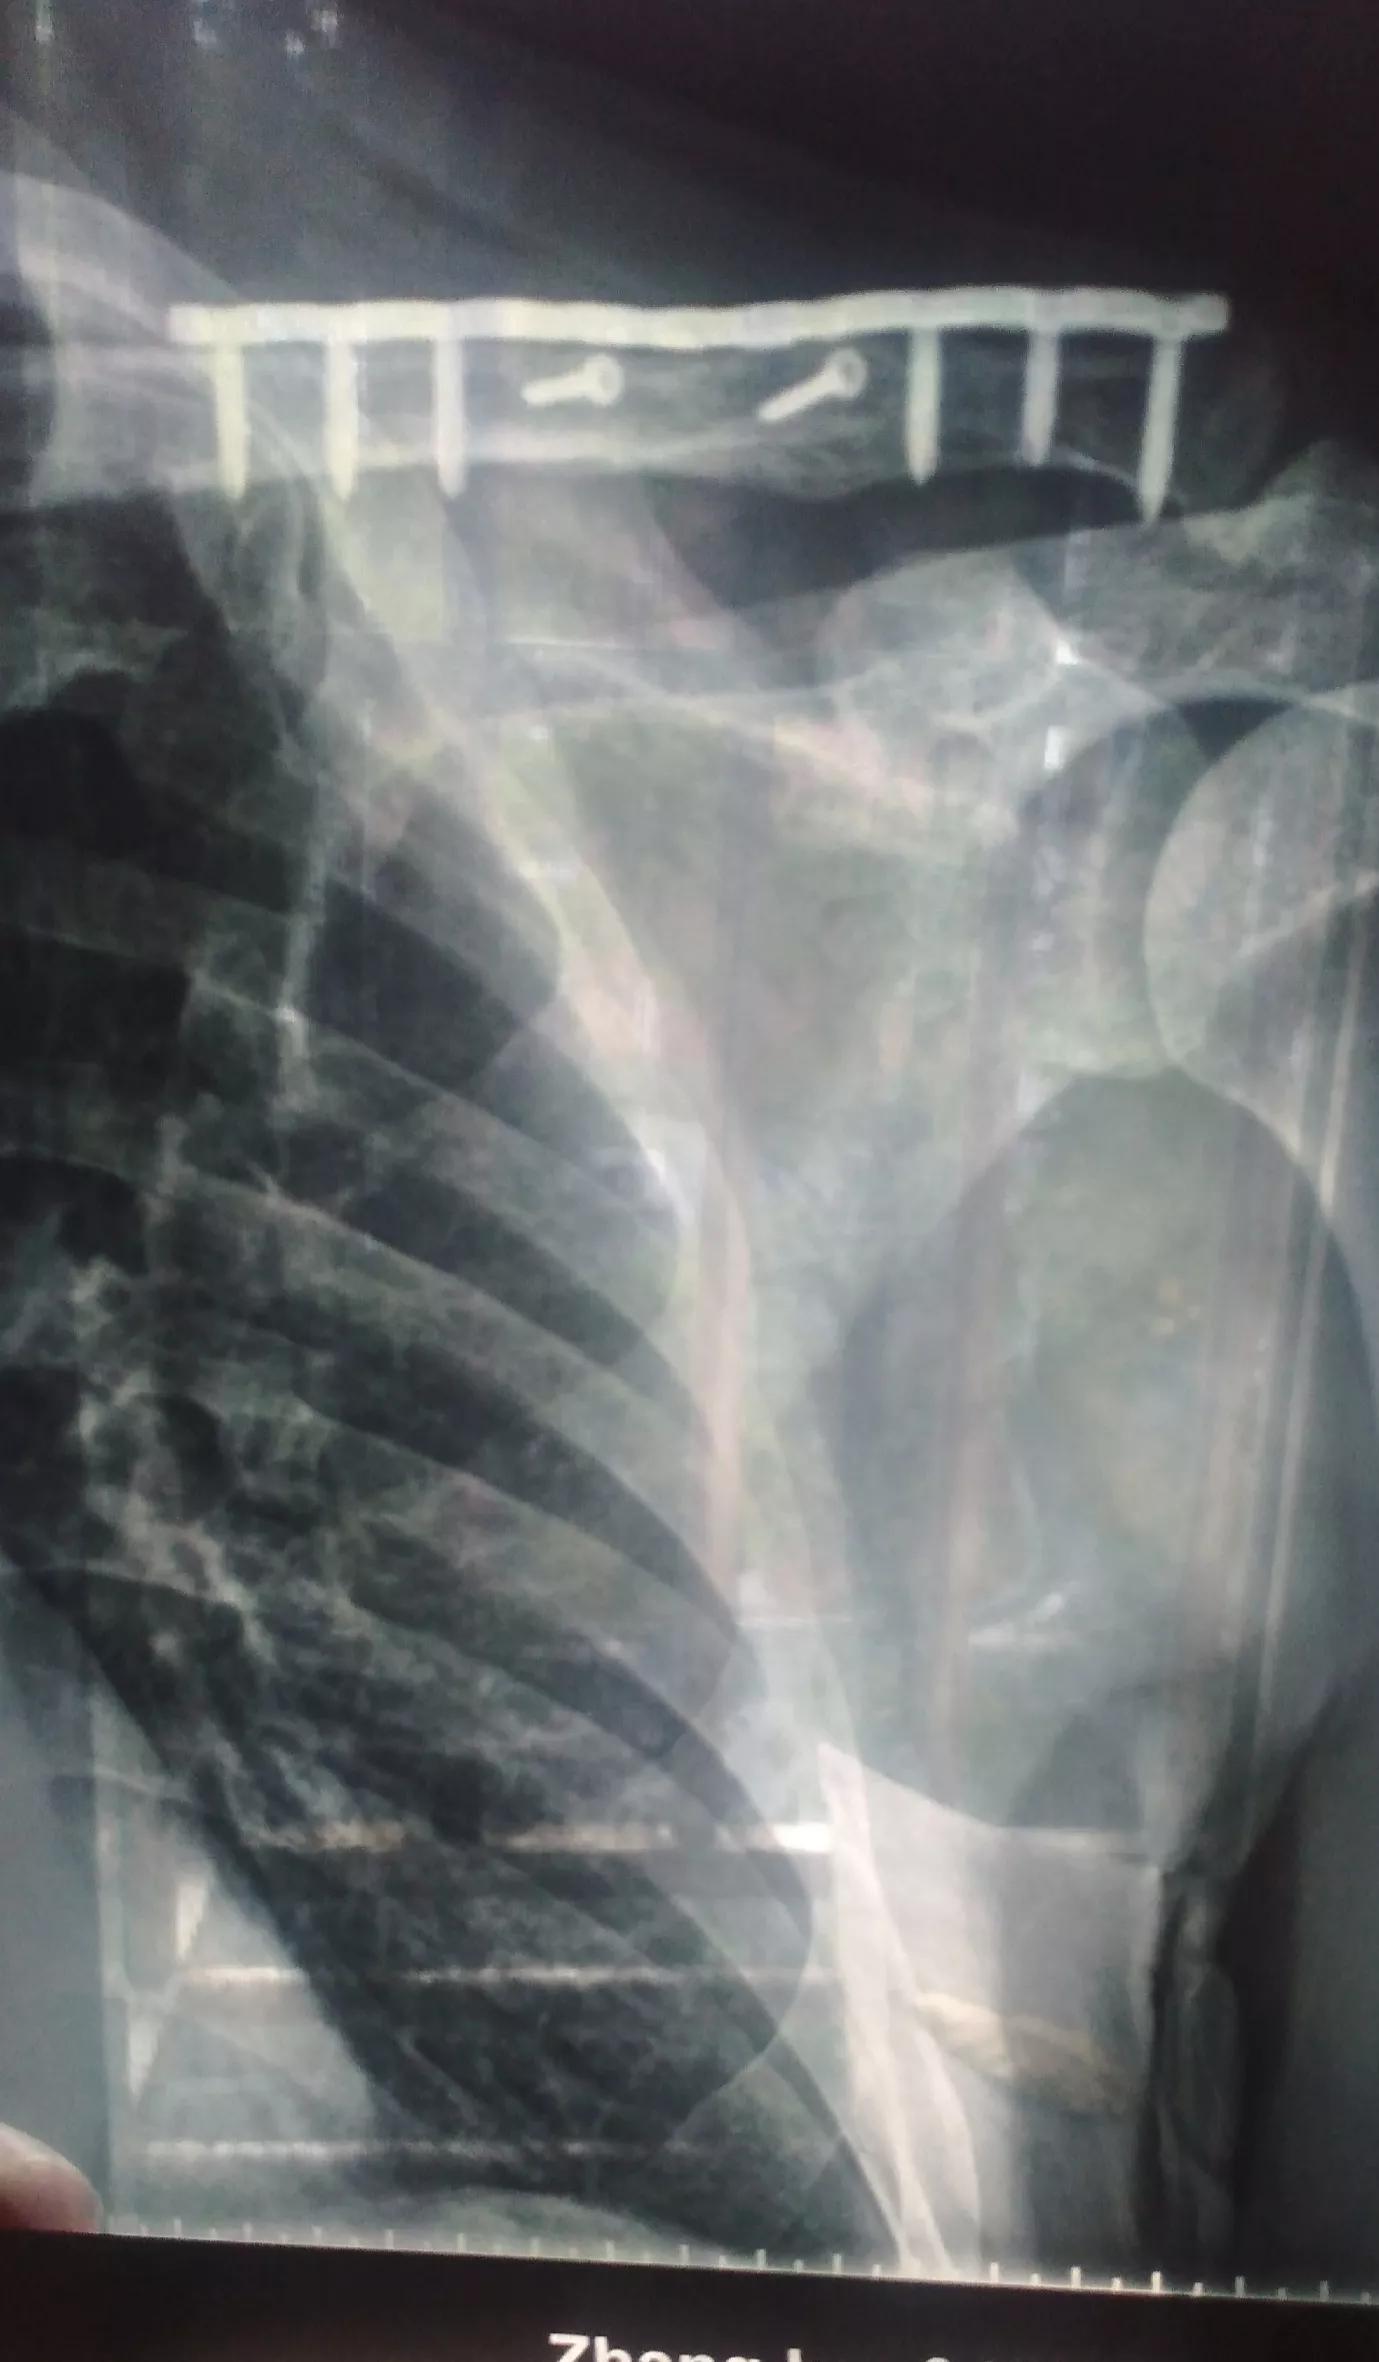

我骑的是摩托车,在买摩托车之前就先考摩托车驾驶证E证,后来学C1,所以我的驾证是C1E。第一辆摩托车是红色的,于2011年摔了右锁骨粉碎性骨折,2013年取内固定(钢板);后来又买辆黑色摩托车骑,于2020年12月底摔了左锁骨粉碎性骨折;今年2022年11月份刚做取钢板手术,现刚出院不久,两次上钢板取钢板共做了四次手术。幸好我都是证照齐全人车合法保险有效,除了人受些罪,经济上没有亏到

我第一次摔跤2011年是“骨折上内骨定”是九级;“骨折”十级;2017年以后细分了,像锁骨骨折只有“远端骨折”才能评上十级;若是交通事故具体伤什么部位能不能评级,评什么级是有严格规定的,能赔偿多少;通过司法鉴定保险公司赔偿,若伤情按规定能评到级的,有的保险公司不需做司法鉴定也是按级赔偿的。